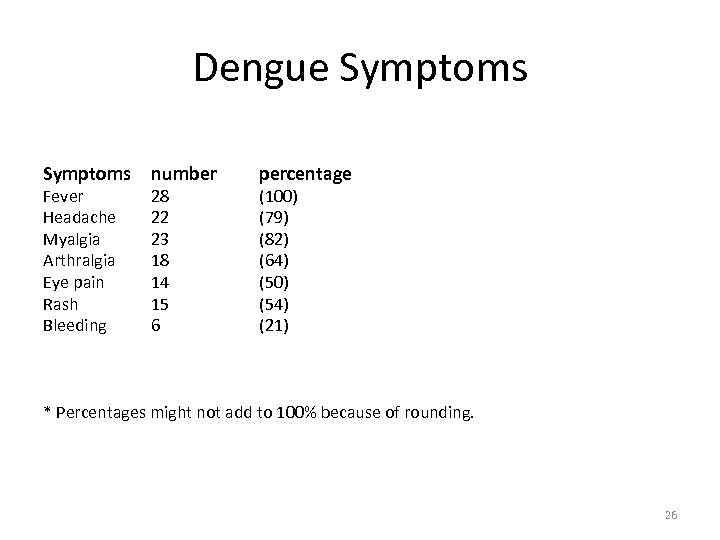

Dengue Symptoms Fever Headache Myalgia Arthralgia Eye pain Rash Bleeding number 28 22 23 18 14 15 6 percentage (100) (79) (82) (64) (50) (54) (21) * Percentages might not add to 100% because of rounding. 26